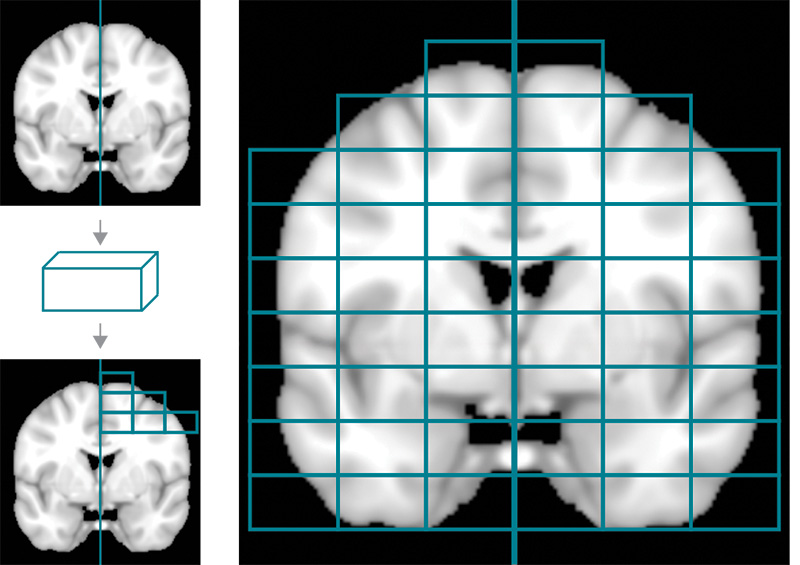

La figura mostra come le scansioni cerebrali ottenute con la risonanza magnetica (MRI) vengono suddivise in volumi rettangolari. Questi volumi, chiamati “patch”, vengono poi usati per costruire una rete cerebrale: ogni patch rappresenta un nodo della rete, e i collegamenti (o link) tra i nodi indicano quanto questi volumi del cervello sono simili tra loro.

(©Asimmetrie-Infn(Hylab))